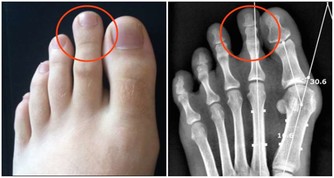

染髮劑一般分為暫時性染髮劑、半持久性染髮劑和持久性(氧化型)染髮劑,絕大多數人使用的是持久性染髮劑。持久性染髮劑含有對苯二胺(PPD),這是目前使用最廣泛的著色劑成分。PPD是一種公認的致癌物質,流行病學調查顯示它可以增加患膀胱癌的風險,特別是黑色染髮劑,含PPD的量相對較高。

染髮劑中的PPD,還能導致過敏。

歐洲國家曾做過調查,普通人群接觸PPD過敏率為0.1%—1.0%,

在泰國高達2.3%,就是說100個用過染髮劑的人起碼2個人過敏。